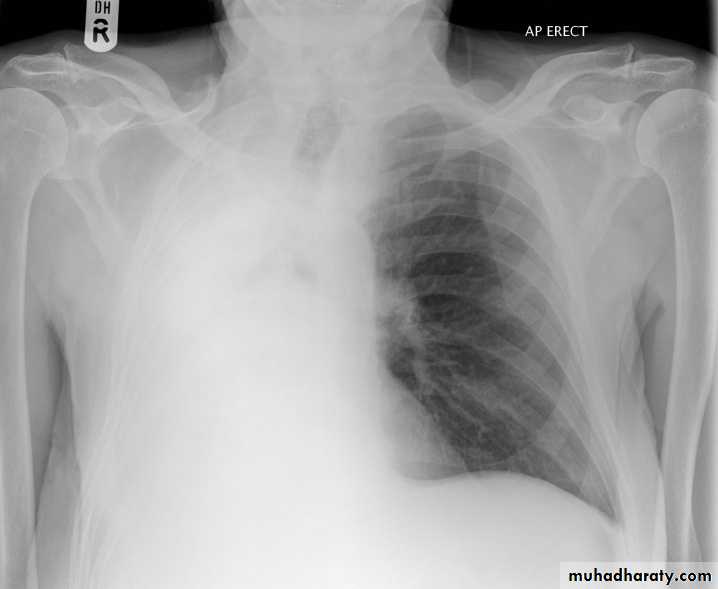

Lymphangitic carcinomatosis:

Lymphangitic carcinomatosis (LC) refers to the diffuse infiltration and obstruction of pulmonary parenchymal lymphatic channels by tumor, usually adenocarcinma from breast, lung, stomach and colon. patient usual presenting complaint is breathlessness.

Chest radiography of a 31-year-old woman showing diffuse interstitial and septal thickening (arrow) in both lungs.

Lymphangitic carcinomatosis